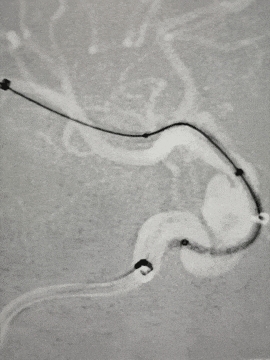

左侧颈内动脉:

Synchro 2导丝和X-T27同轴带CAT5到大脑中M1段远端。

左侧同样路径迂曲,海绵窦III型导致基础支撑不足,Surpass Streamline血流导向密网支架无法到位,至海绵窦段高到位,微导丝和CAT5送高,增强系统支撑,支架顺利跨过虹吸弯到位